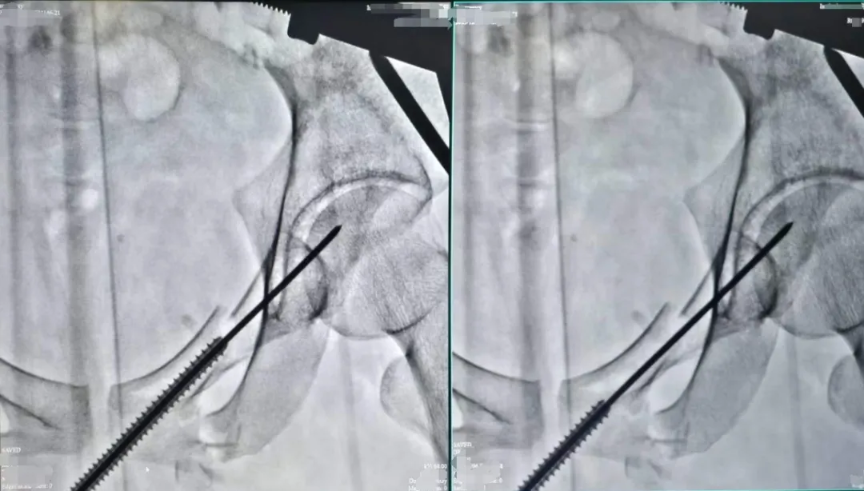

術中透視(上)

針對小陳這樣的案例,使用的經皮恥骨支螺釘內固定術是一種髓內固定技術,在治療骨盆前環損傷中得到了越來越廣泛的應用,常用于恥骨上支骨折和髖臼前柱骨折。經過實踐分析,這是治療單側恥骨骨折的最佳治療方式,具有手術創傷小、術中出血量少、固定強度大、并發癥少及功能恢復快等優點。